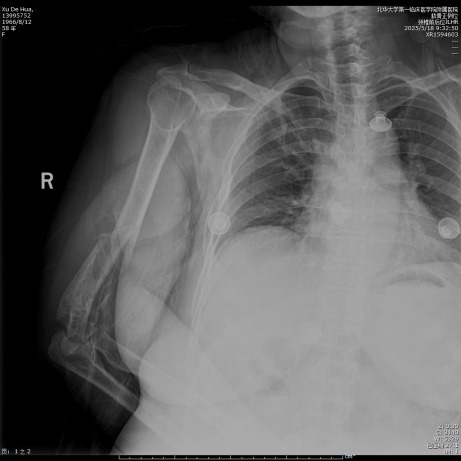

待麻醉生效后,患者取左侧卧位于手术台上,右上肢术区常规消毒,铺无菌单,贴皮肤保护膜。取右上臂中远段后正中入路,纵行切开一长约18.0 cm手术切口,依次切开皮肤、皮下,切开筋膜层,充分显露尺骨鹰嘴,将尺神经分离充分显露后予以保护,应用微型摆锯“V”形截骨尺骨鹰嘴,将尺骨鹰嘴连同肱三头肌腱剥离,湿盐水纱布保护,注意保护桡神经,暴露肱骨中远段,见肱骨中下段螺旋形骨折,分离短缩移位,肱骨滑车、肱骨小头、肱骨内外髁多处骨折线,分离旋转移位,局部骨质缺损,将肱骨中下段、肱骨滑车、肱骨小头、肱骨内外髁骨折复位,克氏针临时固定,后分别于右肱骨远折端内侧、后侧铺放2枚解剖型钢板,注意保护桡神经和尺神经,拧入数枚螺钉固定,C臂透视见钢板及螺钉长度及位置满意(见图2)。并于外髁骨缺损处植入3.0 g β-磷酸钙生物陶瓷不规则颗粒。将截断的尺骨鹰嘴复位后打入两根克氏针临时固定,并应用钢丝“8”字捆绑固定(见图3),活动肘关节,见骨折复位固定确实,关节无异响和绞索。后将尺神经松解前置,见神经松紧带适宜。后清点器械、纱布无误后,冲洗术区,彻底止血,术区留置负压引流管1枚,撒入盐酸万古霉素0.5 g及止血粉于切口内,预防感染及促进止血,应用可吸收性倒刺线2根逐层缝合肌层及皮下,一次性使用皮肤缝合器关闭切口,无菌敷料进行外包扎,石膏托固定肘关节于功能位(90˚屈曲),术毕。手术经过顺利,麻醉效果满意,术中出血量约1200 ml,给予输注ABO血型AB型Rh(D)阳性去白细胞悬浮红细胞2单位,过程中无明显输血不良反应,术后患者呈清醒状态安返病房。

Figure 2. Intraoperative findings and C-arm fluoroscopy with anteroposterior and lateral radiographs

2. 术中外相及C型臂透视正侧位X线片